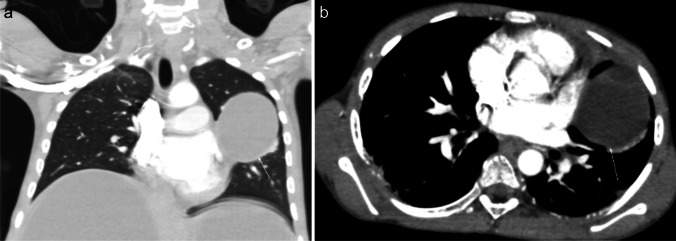

Radiological findings of hypersensitivity pneumonitis vary according to the stage of the disease. Although chest radiography can help identify the disease, CT is increasingly used, as it is more sensitive for subtle ground-glass opacities and identification of fibrosis [69]. In the acute/inflammatory form, CT typically shows patchy or diffuse bilateral ground-glass opacities, small centrilobular nodules, lobular areas of reduced attenuation and vascularization (i.e., mosaic attenuation), and air trapping on expiratory images (Fig. 9). Thickening of the interlobular septa, traction bronchiectasis, and a subpleural honeycomb pattern are signs of chronic/fibrotic form. The lung bases are typically spared [70].

Fig. 9.

Axial (a) and coronal (b) contrast-enhanced lung window computed tomography images in a 9-year-old girl with a 3-month history of chronic dry cough, wheezing, and loss of weight demonstrate patchy bilateral ground-glass opacities, small centrilobular nodules, lobular areas of reduced attenuation and vascularization (i.e., mosaic attenuation), and interlobular septal thickening with sparing of the lung bases. No associated features of chronic lung disease. Lung biopsy confirmed hypersensitivity pneumonitis. On further investigation, her mother also had similar clinical symptoms. The family had started breeding pigeons 6 months prior. When the antigen was removed, the child’s symptoms completely resolved, and follow-up chest radiography performed 3 months later (not shown) was normal

There are no pathognomonic radiographic findings for pulmonary hemorrhage. On radiographs, localized hemorrhage may appear as patchy alveolar opacities or dense consolidation. Diffuse hemorrhage appears as a symmetric diffuse hazy ground-glass pattern, which typically predominates in the lower lung zones with sparing of the apices and costophrenic angles. Diffuse pulmonary hemorrhage secondary to vasculitis may have an asymmetric or patchy distribution [73]. A characteristic feature of hemorrhage is rapid resolution of radiological opacities over 2–3 days, unless hemorrhage is ongoing or repetitive [71]. As hemorrhage clears, an interstitial pattern with thickening of the interlobular septa may emerge. Within a couple of weeks, chest radiographs typically normalize. However, following repeated episodes of pulmonary hemorrhage, a reticulonodular pattern of interstitial fibrosis develops. The CT findings of pulmonary hemorrhage correlate well with chest radiography. CT is a useful adjunct to radiography in the evaluation of localized pulmonary hemorrhage for depiction of the underlying disease and is also a valuable imaging modality for embolization planning in patients with massive hemorrhage (Fig. 10). Findings suggestive of pulmonary vasculitis on CT include fluffy, centrilobular, perivascular densities found centrally and peripherally. Patients with a normal chest radiograph and a high suspicion of pulmonary hemorrhage may benefit from CT for the diagnosis and differentiating it from other potential diagnostic considerations [71].

Fig. 10.

Axial contrast-enhanced lung window computed tomography image in a 12-year-old girl with granulomatosis, polyangiitis, and pulmonary hemorrhage who presented with hemoptysis and anemia. The image shows interlobular septal thickening superimposed on areas of ground-glass opacity, resulting in a characteristic crazy-paving pattern